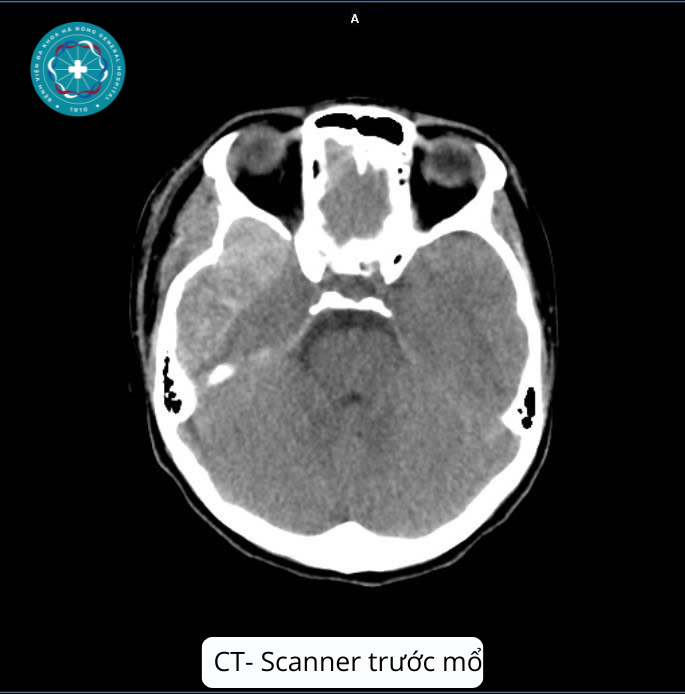

Bệnh nhân vào viện sau tai nạn giao thông trong tình trạng đau đầu dữ dội, quên sự việc đã xảy ra, ý thức giảm dần, Glasgow 13 điểm, vùng đỉnh trái sưng nề, chảy máu. Qua thăm khám lâm sàng và hình ảnh chụp CT-Scanner sọ não, các bác sĩ phát hiện khối máu tụ ngoài màng cứng vùng thái dương đỉnh trái với kích thước rất lớn (78x16x82 mm), kèm tụ khí nội sọ, vỡ xương thái dương trái.

Hình ảnh chụp CT bệnh nhân trước khi mổ (nguồn bệnh viện).